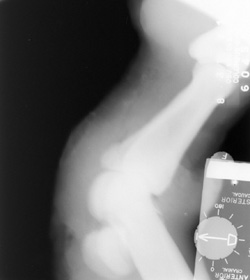

Click to enlarge Click to enlarge

Motion: Patient motion resulting in a blurred image.